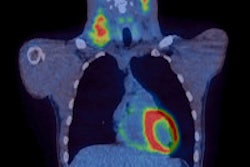

Contrast-enhanced ultrasound of the spleen proved better than both CT and PET for staging nodules in patients with Hodgkin's lymphoma, according to a study published by Italian researchers in the May edition of Radiology.

Spleen involvement occurs in 10% to 30% of patients with Hodgkin's lymphoma, with staging usually performed by CT or PET, which are thought to be the most accurate modalities. Ultrasound without contrast has not typically been used for this application, according to the study team from the Federico II University Medical School in Naples.

CT was able to detect malignant nodules in 13 patients, while FDG-PET also found malignant nodules in 13 patients. Contrast-enhanced harmonic ultrasound, however, detected malignant nodules in 30 patients.

Compared to contrast-enhanced harmonic compound ultrasound findings, the sensitivity of both CT and FDG-PET in detecting splenic malignancy was 43% (13 of 30; 95% CI, 0.26-0.62), yielding a false-negative rate of 57% (17 of 30; 95% CI, 0.38-0.74), according to the authors.

"Both CT and FDG-PET provided false-negative results in 17 of 30 patients compared with contrast-enhanced harmonic compound US, the results of which translated into disease upstaging in 13 patients," the authors wrote.

In other results, all three imaging techniques correctly classified 10 of the 13 patients with nodules greater than 1 cm. Three patients, however, had normal findings on both CT and FDG-PET. Of the 17 patients with nodules 1 cm or smaller, CT and FDG-PET identified lymphoma involvement in only three cases.

The researchers concluded that clinicians should not rely solely on conventional diagnostic procedures to exclude subdiaphragmatic disease in patients with newly diagnosed Hodgkin's lymphoma, given the possibility of cryptic nodular infiltration in spleens that appear negative on CT and FDG-PET studies.

"Harmonic compound US with contrast enhancement for the characterization of possible nodules provides a higher sensitivity than does CT or FDG-PET in the detection of splenic involvement by Hodgkin's lymphoma," the authors wrote.